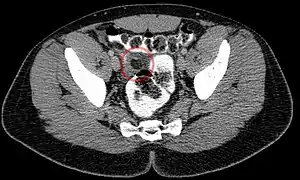

| Epiploic appendagitis seen on CT scan. | |

Ultrasound and CT scans are the normal means of positive diagnosis of epiploic appendagitis. Ultrasound scans show "an oval, non-compressible hyperechoic mass with a subtle hypoechoic rim directly under the site of maximum tenderness".[5] Normally, epiploic appendages cannot be seen on CT scan.[5] After cross-sectional imaging and the increased use of abdominal CT for evaluating lower abdominal pain, EA is increasingly diagnosed. Pathognomonic CT scan data represent EA as 2–4 cm, oval shaped, fat density lesions, surrounded by inflammation. Contrasting with diverticulitis findings, the colonic wall is mostly unchanged.

Abdominal CT scan, epiploic appendagitis (circle)